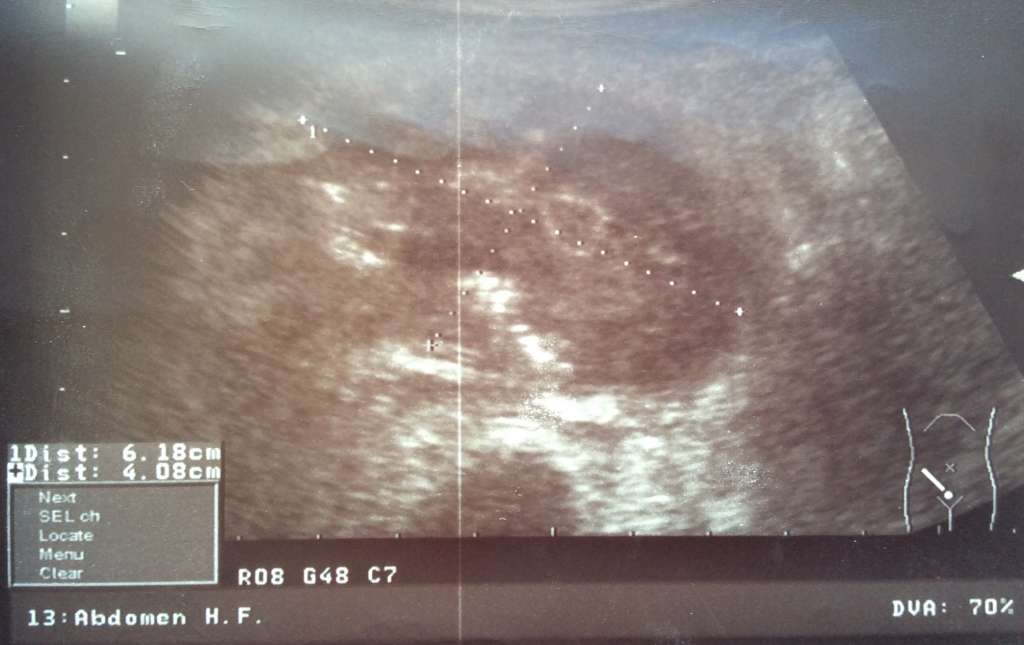

УЗИ Опухоль головки поджелудочной железы фото